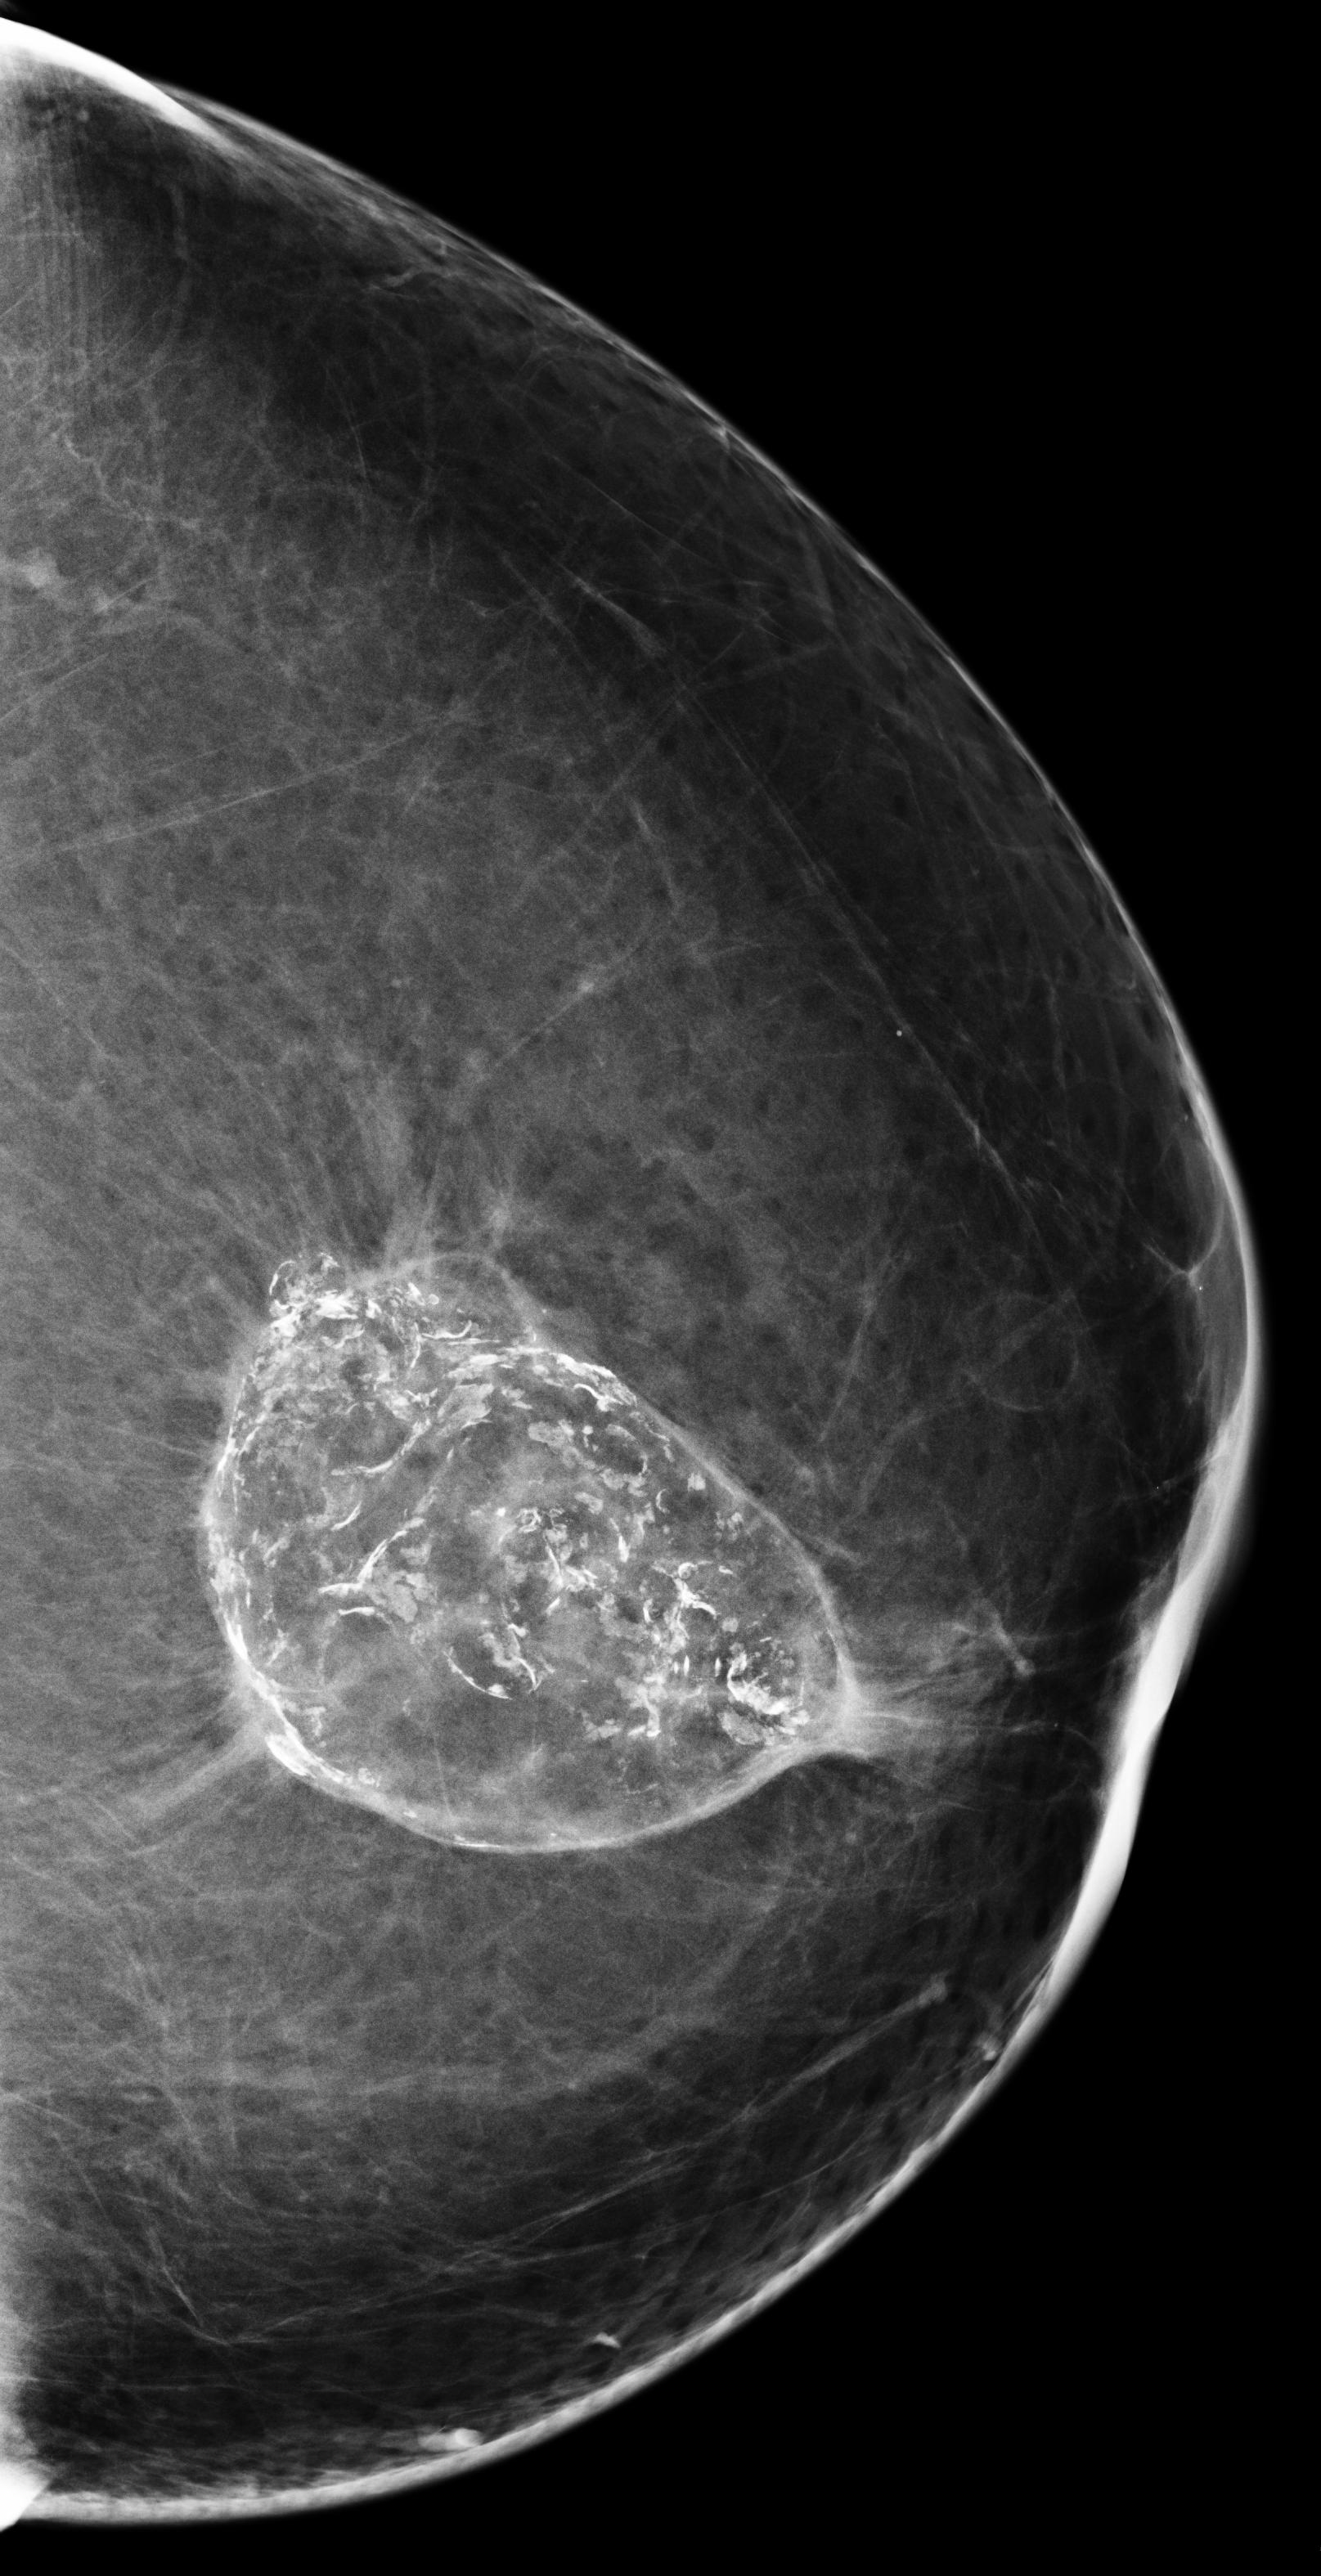

[\capbeside\thisfloatsetupcapbesideposition=left,top,capbesidewidth=6cm]figure[13cm] prior latest highlight prior latest L-CC Refer to caption Refer to caption Refer to caption L-CC Refer to caption Refer to caption L-MLO Refer to caption Refer to caption Refer to caption L-MLO Refer to caption Refer to caption (a) (b)

Figure 3: Test examples where AlignLocalCompare performs better than the single-exam baseline. A breast with a malignant finding shown in (a) (malignant finding is highlighted with red) and one with a benign lesion shown in (b). AlignLocalCompare predicts malignancy with 0.97 probability for (a) and 0.04 for (b), whereas the baseline predicts 0.73 for (a) and 0.24 for (b). There is about a year gap between two exams for both patients.